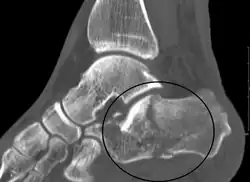

| X-ray of a fractured calcaneus | |

| Diagnostic method | Based on symptoms, X-rays, CT scan[1] |

It usually occurs when a person lands on their feet following a fall from a height or during a motor vehicle collision.[2][1] Diagnosis is suspected based on symptoms and confirmed by X-rays or CT scanning.[1]

Conventional radiography is usually the initial assessment tool when a calcaneal fracture is suspected. Recommended x-ray views are (a) axial, (b) anteroposterior, (c) oblique and (d) views with dorsiflexion and internal rotation of the foot. However, conventional radiography is limited for visualization of calcaneal anatomy, especially at the subtalar joint. A CT scan is currently the imaging study of choice for evaluating calcaneal injury and has substituted conventional radiography in the classification of calcaneal fractures.[13] Axial and coronal views are obtained for proper visualization of the calcaneus, subtalar, calcaneocuboid and talonavicular joints.